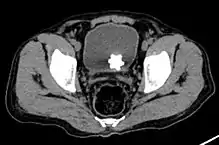

Large jackstone in the bladder of a 60-year-old man. Stone was removed by open cystolithotomy

The diagnosis of bladder stone includes urinalysis, ultrasonography, x rays or cystoscopy (inserting a small thin camera into the urethra and viewing the bladder). The intravenous pyelogram can also be used to assess the presence of kidney stones. This test involves injecting a radiocontrast agent which is passed into the urinary system. X-ray images are then obtained every few minutes to determine if there is any obstruction to the contrast as it is excreted into the bladder. Today, intravenous pyelogram has been replaced at many health centers by CT scans. CT scans are more sensitive and can identify very small stones not seen by other tests.[8]